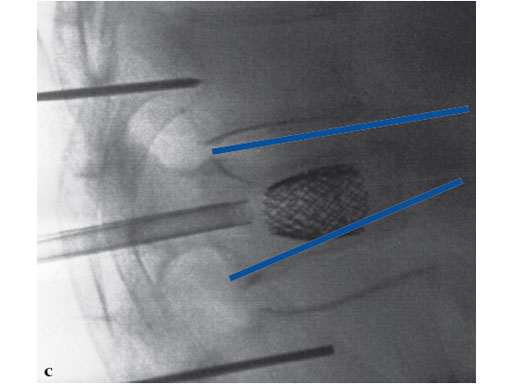

A 78-year-old man with back pain after a simple fall. An MRI showed a subacute fracture with a collapsed vertebral body of L1. A VB S was used for height restoration. The patient was pain-free immediately after the intervention.

Fig 1-4 Intraoperative images.